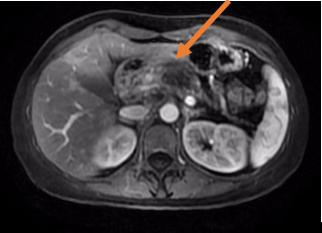

海扶刀在医学影像引导下,将体外低强度超声波聚焦于体内病灶,如同长了眼睛一般精准定位肿瘤。继而形成高能量的焦点,瞬态的高温(60℃—100℃)让肿瘤迅速凝固性坏死,而肿瘤以外组织却不受到明显损伤。通过控制焦点的三维组合运动,海扶刀以“点-束-片-块的”方式最终完成对整块靶组织的适形消融治疗。也就是说,海扶刀能“隔空打穴”,无需开刀,不会出血,通过超声波精准消灭肿瘤。

一位胰腺癌患者初诊时已是晚期,无根治性手术指征,来到青大附院就诊。传统治疗模式是以化疗为主,联合止痛、营养治疗。由于患者营养状态较差,治疗前评估其对化疗的耐受较差。在治疗肿瘤和担心副作用之间,患者和家属无数次徘徊和犹豫。海扶治疗为患者提供了一种新选择。肿瘤内科主任于壮组织会诊,制定详细方案,在麻醉科的配合下,于宁主任为患者完成全麻下胰腺病灶超声消融。手术后复查,该患者胰腺病灶“完美”消融,疼痛逐渐消失,恢复进食,体力状态较治疗前明显好转。接下来,患者在肿瘤内科接受了化疗,有足够的营养状态做支撑,没有出现严重的化疗相关副反应,肿瘤得到了长期的控制,生活质量也得到了极大改善。

胰腺癌被称为“癌中之王”,虽然发病率不高,但死亡率很高。患者初次诊断时大多已经发展为局部晚期或出现转移,失去手术机会。海扶刀治疗给胰腺癌患者带来多方面的改善。一是能快速缓解疼痛。九成伴有疼痛的患者通过一次治疗就能够有效缓解疼痛,明显改善生活质量。二是快速让肿瘤坏死,再联合化疗、放疗等其他治疗方式,大大延长患者生存时间和质量。近3年的研究结果显示,局部晚期(尚未转移)胰腺癌患者应用上述联合方式治疗后平均生存时间已超过2年。“癌中之王”尚且能被遏制,海扶刀对恶性肿瘤治疗效果可管窥一豹。